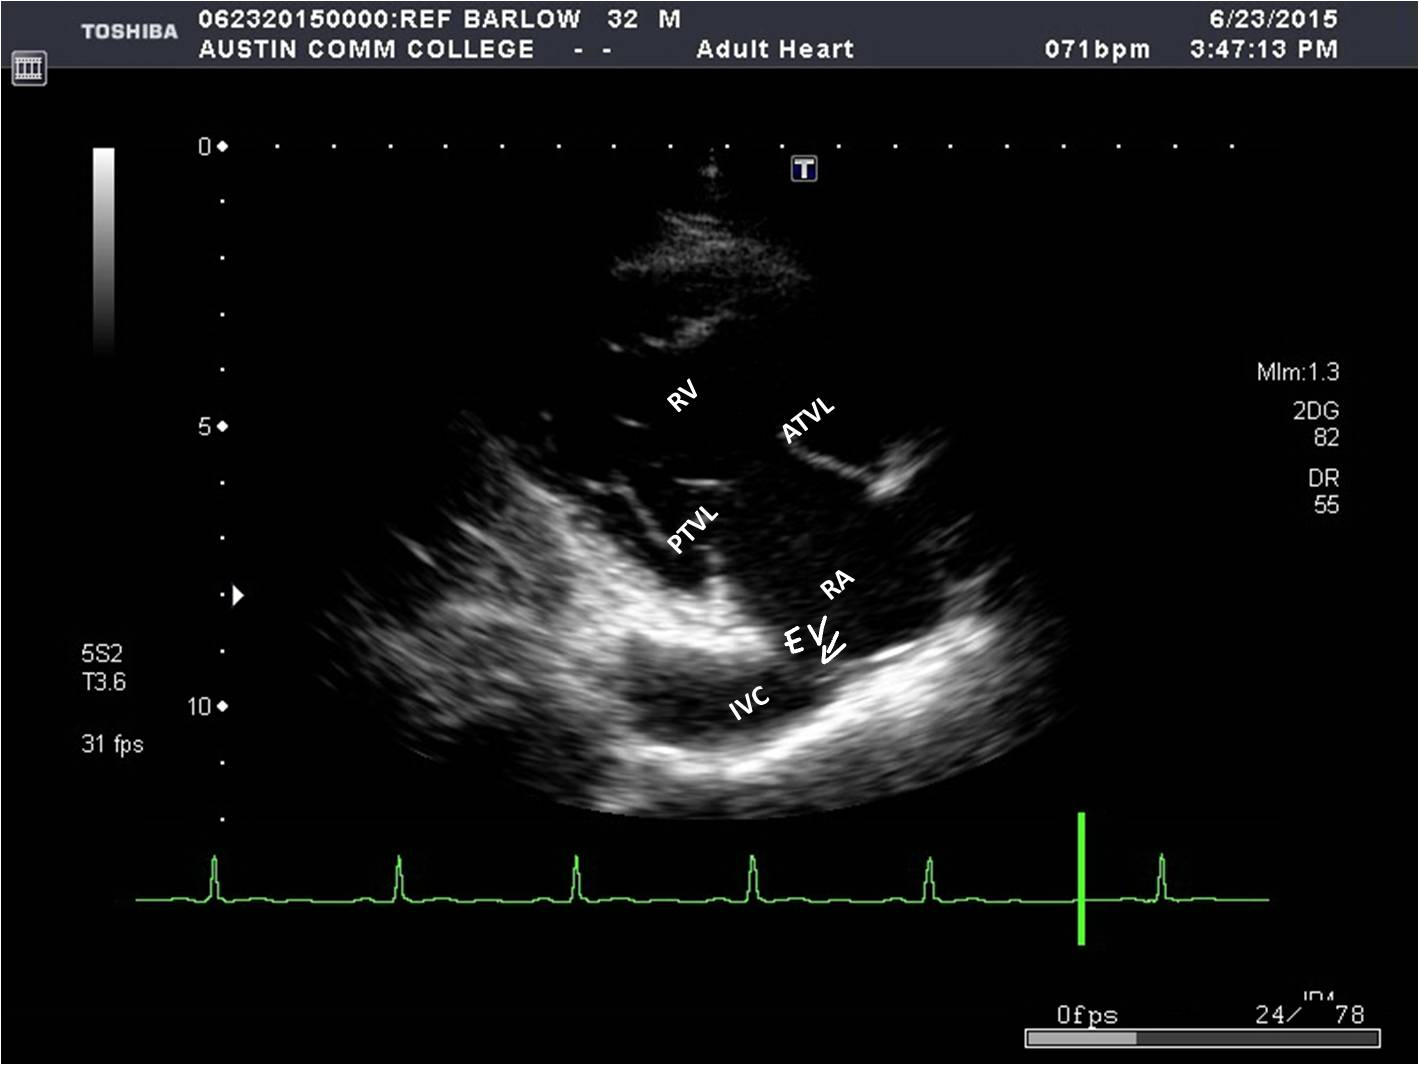

What structures can be seen in a parasternal LAX RVIT?

* RA

* RV

* Tricuspid valve

* Coronary sinus

* IVC

* Eustachian valve

* RV

* Tricuspid valve

* Coronary sinus

* IVC

* Eustachian valve